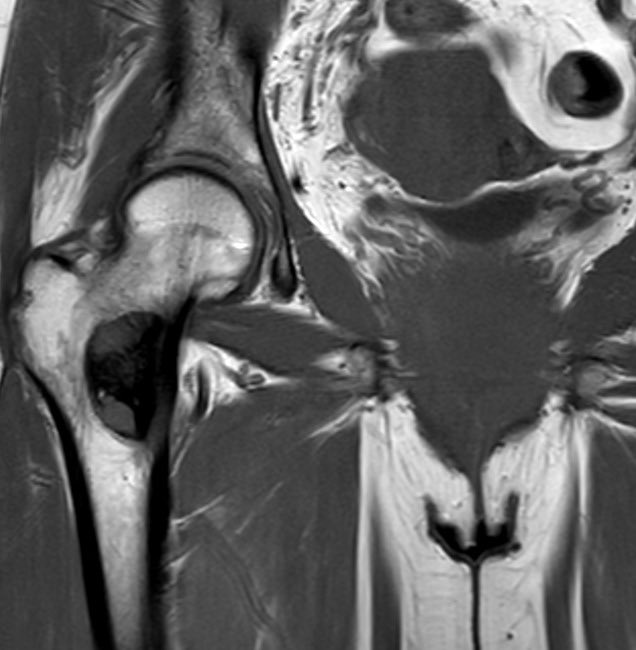

A beautiful Stener lesion passing through your timeline to make your day better! Society of Skeletal Radiology SSR_RWG RSNA International Skeletal Society | ISS ACRadiologia Skeletal Radiology European Society of Musculoskeletal Radiology